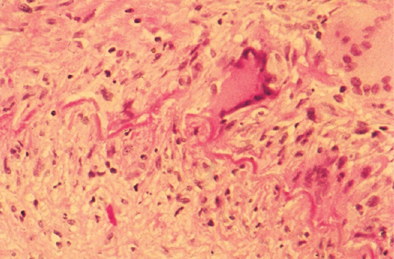

thoracic aorta with aldehyde fuchsin stain

cystic medial necrosis (dissecting aneurysm). focal loss of elastic and muscle fibers in the aortic media leads to cystic spaces filled with pools of metachromatic myxoid material